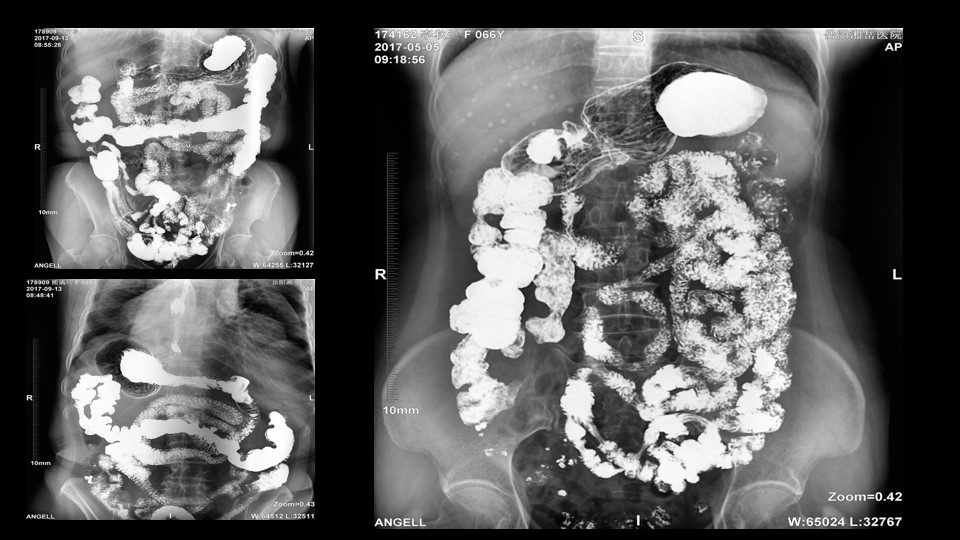

会议开始,岳阳市医学会放射分会副主委、湘岳医院放射科蔡雨主任,结合自身在放射影像的20多年经验,为参会嘉宾分享了动态DR在消化道造影中的应用价值。作为动态DR用户,蔡雨主任结合动态DR的实际拍片与操控经验,分享了动态DR技术在相关群体疾病检查上的独到优势和人文关怀。蔡雨主任说到:“随着内镜技术的发展以及CT、MR的发展,消化道造影在减少,但是这并不意味着消化道造影的价值在下降。以老年人为例,很多老年群体都患有严重的心肺疾病、或者消化道畸形,很多老年人本身就有糖尿病、高血压等等综合疾病,传统内镜的检查对于这类群体来说是一件难以忍受的痛苦,而动态DR的多项创新技术让这类群体的消化系统疾病筛查变得更为人性和精准。任何一个好的消化道造影,一定是患者、诊断医生、临床医生三方满意的结果。广东会科技动态DR技术利用900万像素高清拍片、大幅面透视、高清点片、视频保存与回放等核心功能,完全满足临床对消化道气钡双重造影检查的需要。图像质量全面超越以往模拟胃肠机、影增数字胃肠机”。蔡雨主任全面演示了动态DR在食道造影、上消化道造影、小肠双对比造影、结肠气钡双对比造影中的应用,通过动态DR可以清晰获得临床诊断和评估的图像依据。

▲蔡雨主任使用动态造影图像示例